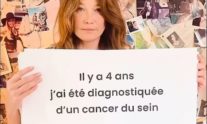

Κάρλα Μπρούνι: «Η ετήσια μαστογραφία με έσωσε από την μαστεκτομή»

Το μήνυμα του πρώην σούπερ μόντελ με αφορμή τον Οκτώβριο που είναι Μήνας Ενημέρωσης για τον Καρκίνο του Μαστού.